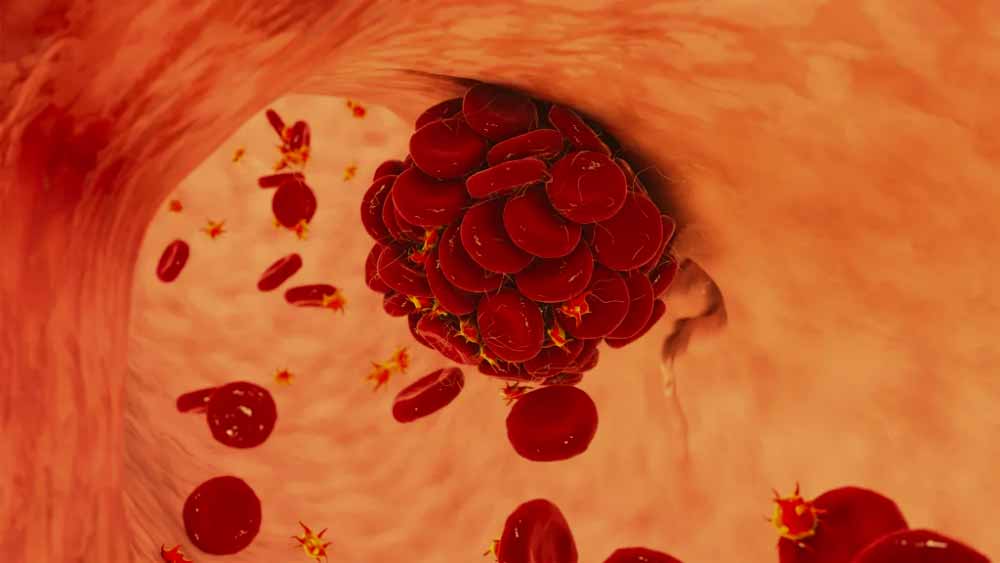

Najpogostejša vrsta pljučnega embola je krvni strdek, po navadi takšen, ki nastane v veni noge ali medenice. Krvni strdki radi nastajajo, če kri teče počasi ali se sploh ustavi, to pa se lahko zgodi v nožnih venah pri človeku, ki dolgo ostaja v nespremenjenem položaju.

Slika: AI prikaz pljučne embolije.

Ko se začne spet gibati, se lahko krvni strdek odtrga. Mnogo redkeje nastanejo strdki v venah rok ali v desnih votlinah srca. Ko se strdek v veni enkrat odtrga in ga kri odnese, po navadi pripotuje v pljuča.

Slika: Prikaz formacije krvnega strdka.